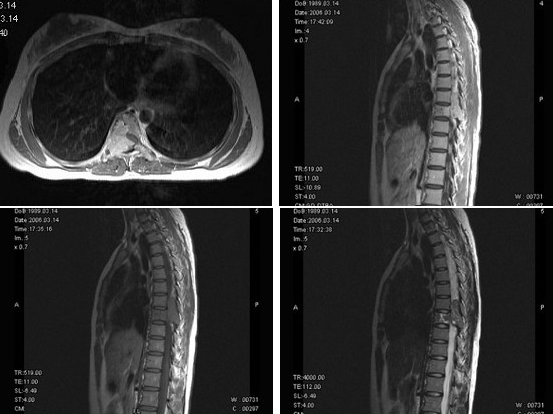

女,18岁,腰以下麻木,双下肢无力,行走困难,PE://双下肢肌力IV+级,肌张力高,腱反射活跃,T3以下痛觉减退,请根据所提供图像,选择最可能的诊断()

A:神经鞘瘤

B:骨母细胞瘤

C:骨巨细胞瘤

D:脊膜瘤

E:淋巴瘤